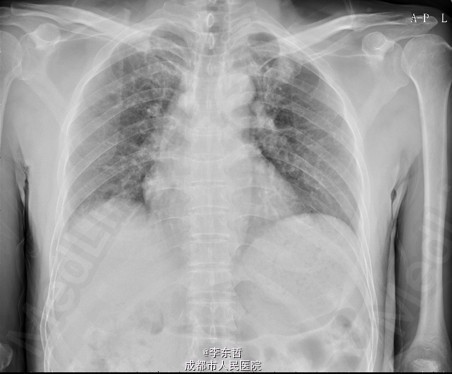

患者男,62岁,因“双髋疼痛4年,加重伴活动受限1年”入院。病员诉入院前4年无明显诱因出现双侧髋部疼痛,行走后疼痛加重,疼痛能忍受,双侧髋部无红肿,皮温不高,无畏寒、发热,休息后疼痛能自行缓解,无夜间疼痛,在当地医院行止痛药内服、理疗治疗,疼痛稍缓解。逐渐加重,1年前双侧髋部疼痛、跛行明显加重,左髋活动受限,行走困难,给予对症治疗症状无明显改善,遂到我科门诊就诊,X线片提示:双侧股骨头坏死,建议手术治疗,故于今日以“双侧侧股骨头坏死”收入我科进一步治疗。

查体:生命体征平稳,心肺腹未见异常;跛行,双左下肢较右下肢短缩1cm,左、右腹股沟中点深压痛,左、右髋叩击痛,左髋屈20°,伸0°,外展10°,内收10°,右髋屈60°,伸0°,外展20°,内收20°。双髋内、外旋活动受限,诱发疼痛,左侧重。 辅助检查:x线片示双侧股骨头坏死、塌陷变形,左侧明显,左髋半脱位。

初步诊断:1、左侧股骨头坏死伴内收肌挛缩(Ficat IV期);2、右侧股骨头坏死(Ficat IV期);3、右膝骨关节炎伴外翻畸形;入院后积极完善术前检查及准备,择期行手术治疗。